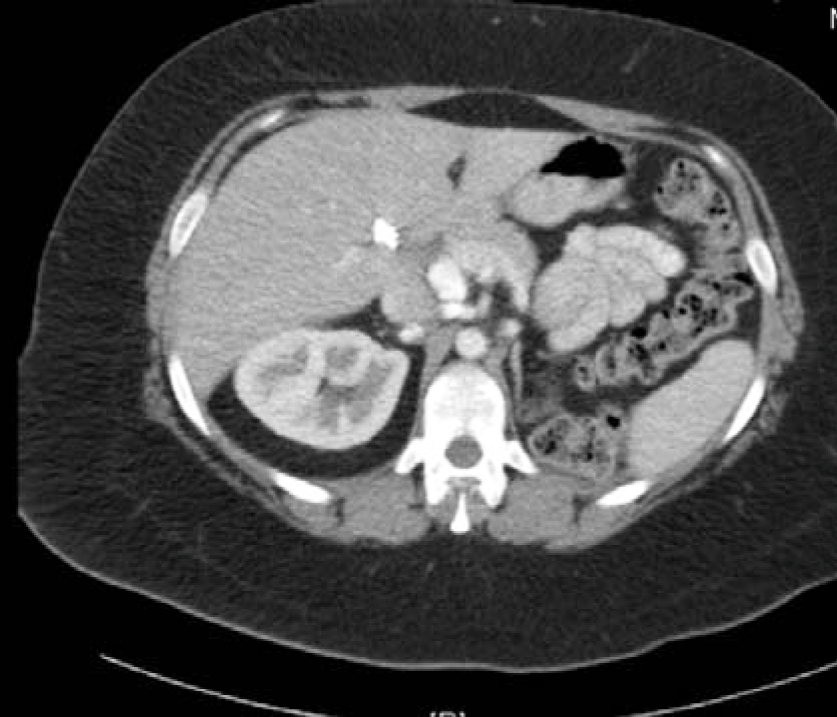

A 58-year-old female with no significant PMH, presented to the ER with acute onset abdominal pain, nausea, vomiting and diarrhea for one day. Patient was in her usual state of health eating and drinking normally, when she started having diffuse abdominal pain. Initially thought it was “gas pain”, but progressed to 9/10 pain throughout the day. Her pain was also accompanied by nausea, multiple episodes of vomiting and diarrhea. A CT abdomen pelvis revealed large bilateral pelvic masses obstructing the colon and ureters (Figure 6 and 7). Soft tissue nodules and ascites also present. Findings were most concerning for peritoneal carcinomatosis (Figure 8 and 9).

Pelvic examination revealed a firm, fixed mass in pelvis with nodularity noted in cul-de sac. Laboratory values significant for a CA 125 of 5121.2. Due to her clinical deterioration and findings of bowel obstruction on CT scan, she underwent exploratory laparotomy with diverting colostomy. At this time, it was decided that patient was not stable enough for cytoreductivedebulking, and will undergo omental biopsy and aspiration of ascites fluid to establish diagnosis. After completion of her transverse loop colostomy, she then underwent resection of the omental nodule and aspiration of ascites. The omental nodule was 5.5 x 3 cm in size and was sent to pathology for frozen section analysis. Results were positive for low-grade serous carcinoma and ascites fluid positive for adenocarcinoma.

Figure 8: CT scan abdomen and pelvis. Multiple liver and splenic implants.

Figure 9: CT scan abdomen and pelvis. Peritoneal implants suggestive of carcinomatosis.